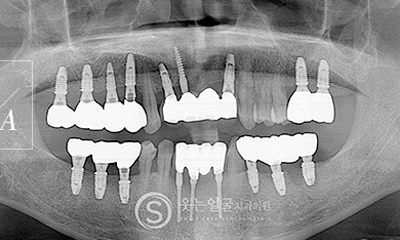

고난이도 임플란트

웃는얼굴치과는 풍부한 경험과 전문성을 바탕으로

일반적인 케이스는 물론,

고난이도의 임플란트 수술까지

안전하게 진행합니다.

뼈 이식이나 발치 즉시 식립 등 까다로운 조건에서도 정밀 진단과

체계적인 시술 시스템으로 환자 맞춤형 치료를 제공합니다.

8천여건의 다양한

임플란트 수술 케이스

다년간 축적된 8,000여 건 이상의

임플란트 수술 경험을 바탕으로,

환자 개개인의 구강 구조와

상태에 최적화된 안전하고 정확한 시술을 제공합니다.